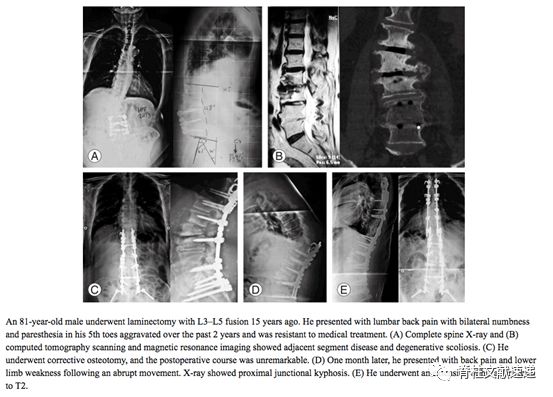

典型病例一:81岁男性患者,15年前接受L3-5椎板切除脊柱融合术,2年前出现腰痛和下肢麻木,诊断椎管狭窄伴脊柱侧弯,行手术治疗,1月后再次出现腰部疼痛和下肢无力,行翻修手术,固定至T2.(矢状面失平衡、PJK发生,主要原因是矫形曲度不合适,过度恢复腰椎前凸所致---笔者注)。